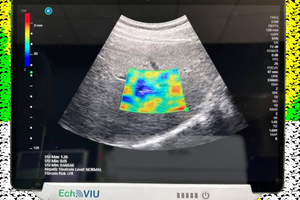

然而目前脂肪肝的檢查方式大多以抽血或超音波檢查為主,非侵入式的超音波檢查,不僅具有輕便、機動性高且容易操作的優點,更讓小朋友檢查時不再害怕抽血時打針的感覺。

長庚大學崔博翔教授研究團隊以「超音波孩童脂肪肝影像診斷系統」榮獲「2022年未來科技獎」殊榮。針對肥胖、過重的孩童與青少年進行研究,若年齡小就有脂肪肝,長大後可能成為肝纖維化高風險族群。平日要保持適度運動,適當控制孩童、青少年飲食,同時也要建立良好生活習慣,才會遠離脂肪肝、肝纖維化的可能,確保肝臟健康。

長庚大學醫學影像暨放射科學系崔博翔教授針對肥胖、過重的孩童與青少年進行研究,若年齡小就有脂肪肝,長大後可能成為肝纖維化高風險族群。平日要保持適度運動,適當控制孩童、青少年飲食,同時也要建立良好生活習慣,才會遠離脂肪肝、肝纖維化的可能,確保肝臟健康。